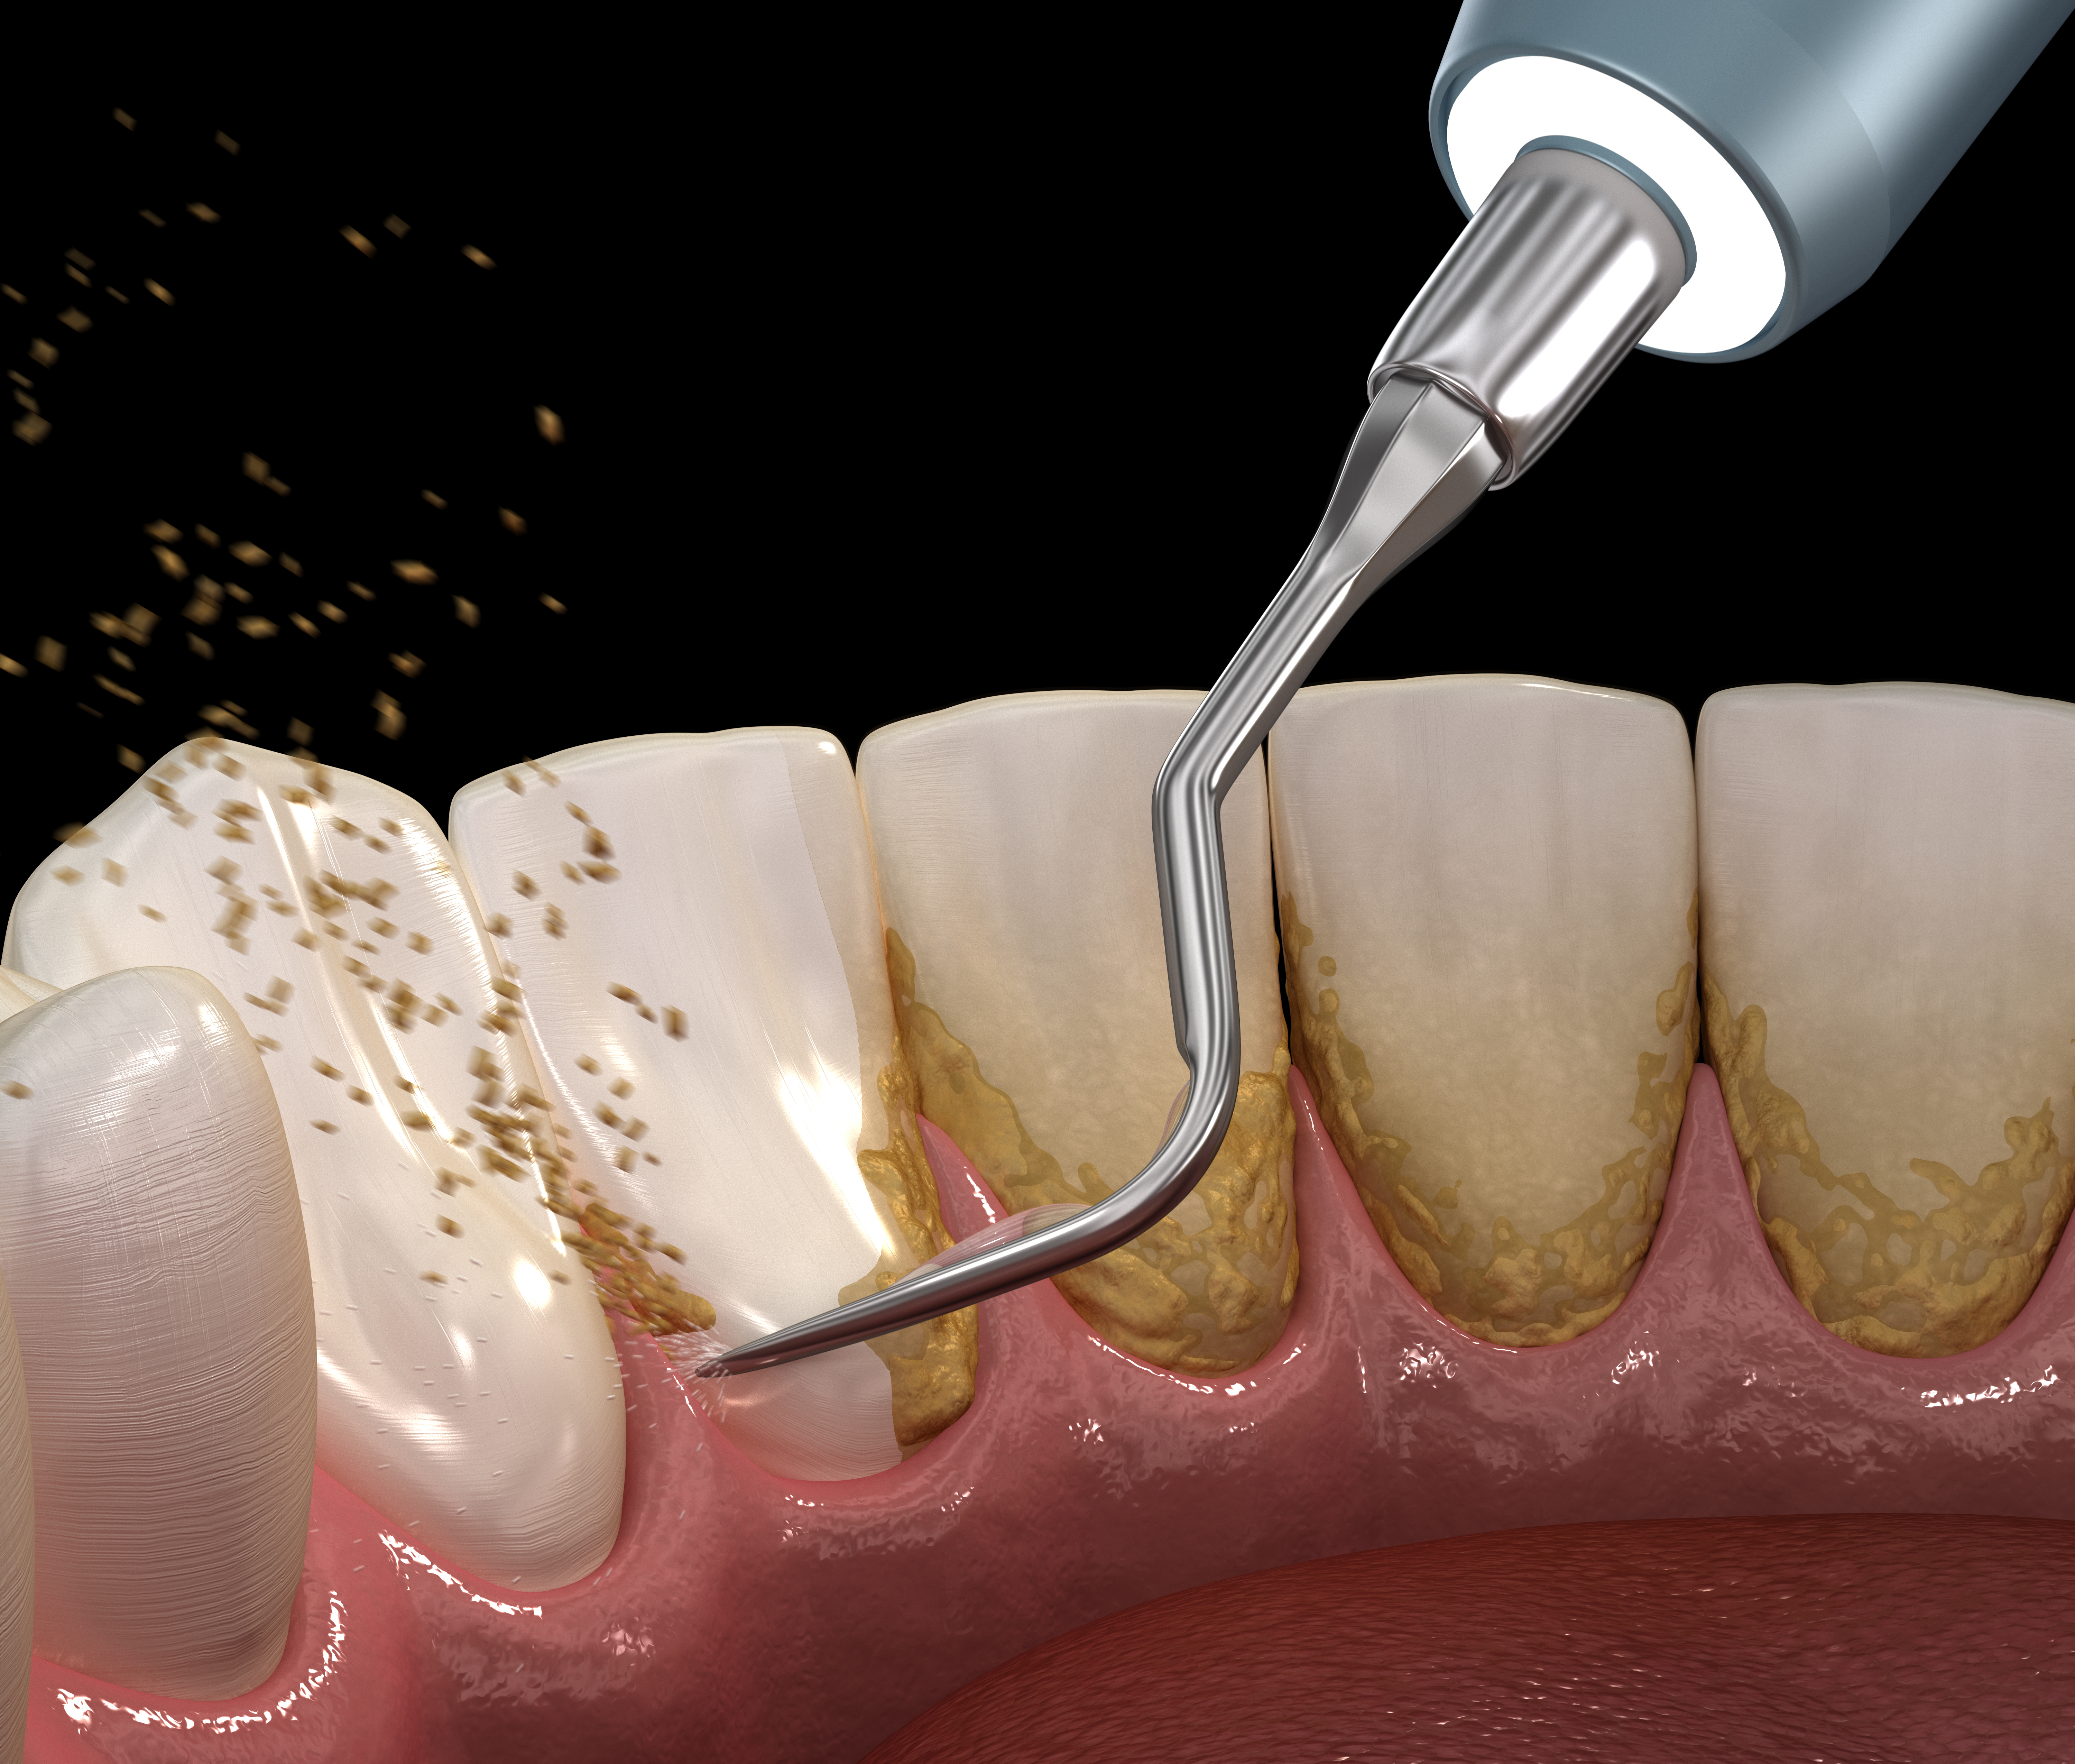

歯周基本治療(初期治療)

歯周基本治療は、歯周病の原因となる歯肉縁上・歯肉縁下の歯石を除去していきます。また、ブラッシング指導を行い、適切なブラッシングを習得していただきます。当院での治療と患者様のブラッシングが相乗効果となり、高い治療成果を生み出します。